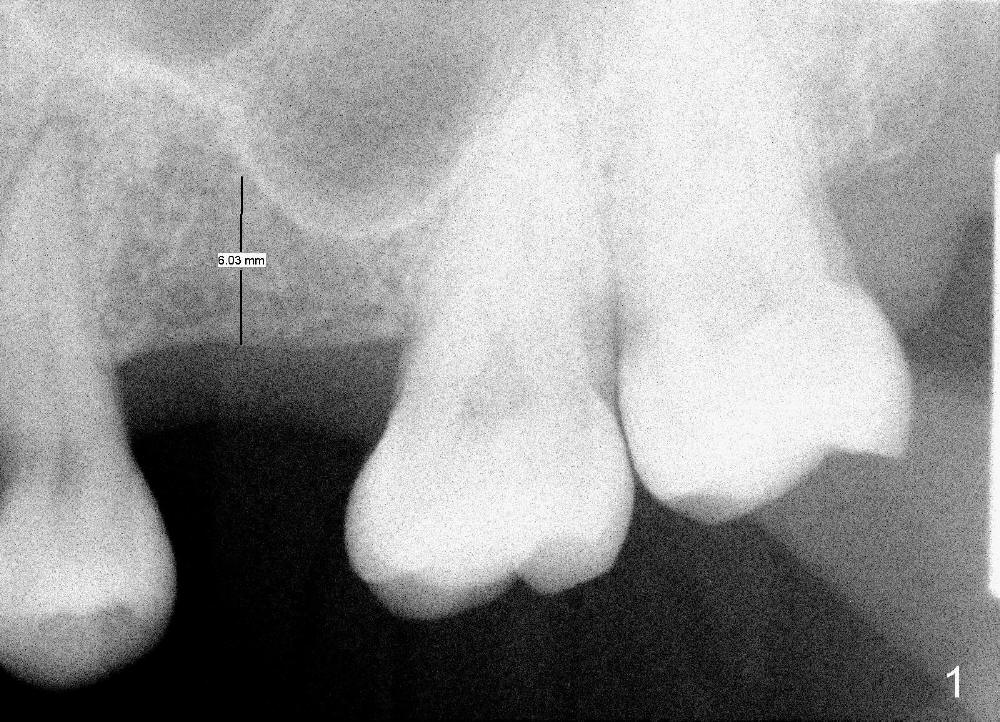

After local anestheisa, an incision is made. The initial osteotomy at the site of the upper left 1st molar is created by 1.6 mm pilot drill at the depth of 6 mm (Fig.1), followed by insertion of bone expanders 2.6, 3.0, and 3.4 mm at approximately 7, 8, and 9 mm deep (Fig.2). A 4.1 mm bone tap is inserted approximately 10 mm without much binding. Mineralized allograft mixed with Osteogen is used for sinus lift. A 4.5x12 mm implant is placed with insertion torque around 35 Ncm (Fig.3). A 5.2 mm healing abutment is placed. The flaps are sutured. The wound is covered by perio dressing.